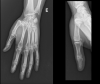

Figure 1

X-ray on emergency department.